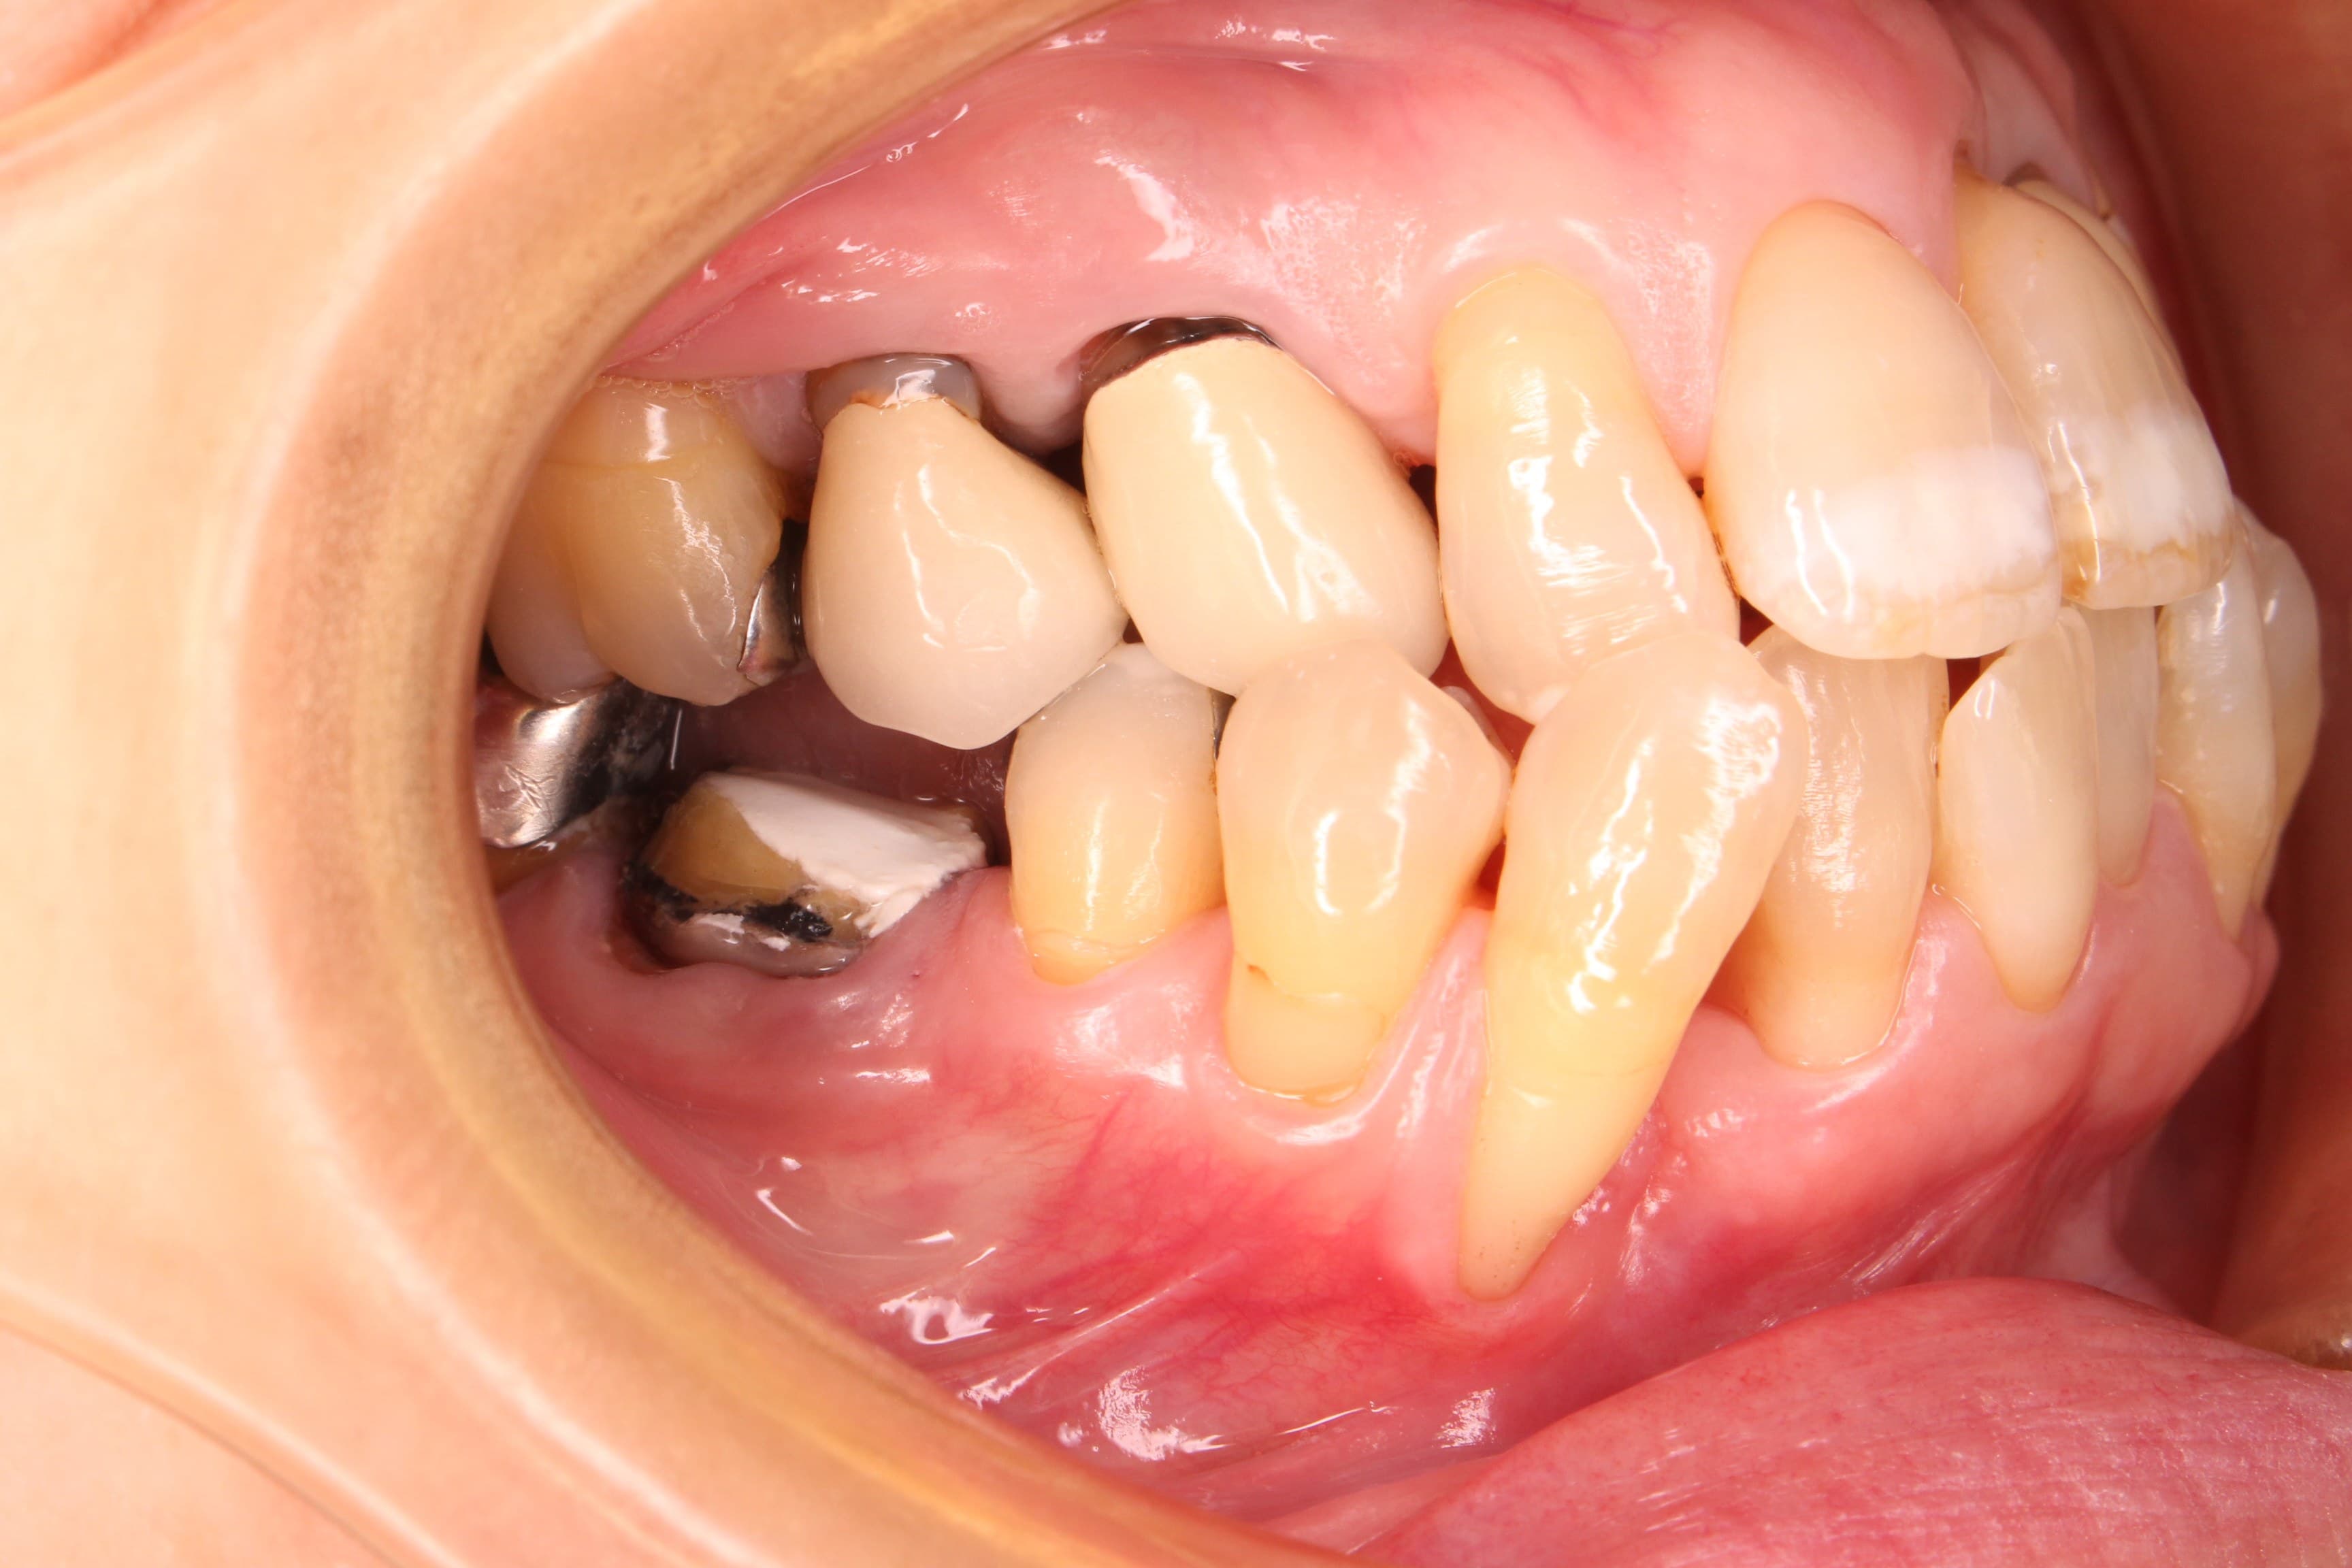

<治療前>

残念ですが、骨が大きく無くなっている所が数か所ありました。

ただ、沼地に家が建たない様に、骨の無い所に歯は建ちません。

沼地をコンクリートに回復させる為には、専門的な処置と同様に「ブラッシング」が大きな役割を担います。

それでも重症化してしまった歯周病は、残念ながら将来的に抜歯のリスクが高く残ってしまいます。